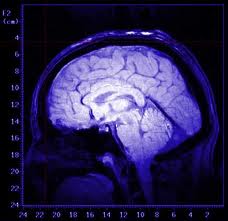

Caratteristiche non comuni del cervello di Einstein potrebbero spiegare le sue notevoli capacità cognitive

Parti del cervello di Albert Einstein sono risultate differenti da quelle della maggior parte delle persone. Queste differenze potrebbero essere…